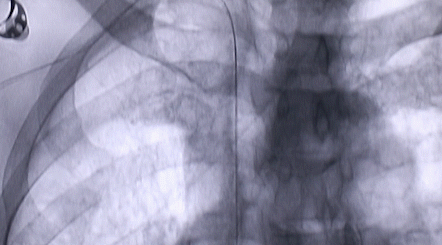

1月12日,西安國際醫(yī)學中心醫(yī)院心臟外科郭穎強主任團隊成功為一名腹主動脈閉塞、右側腎動脈閉塞、左側腎動脈重度狹窄、腹壁淺表動脈側支循環(huán)形成、高血壓病3級(極高危組)合并閉塞性周圍動脈粥樣硬化、急性腎功能不全的老年患者實施腎動脈球囊擴張 腎動脈支架植入術 動脈血栓抽吸術 髂動脈開通術,治好了困擾患者多年的頑固性高血壓。患者目前康復良好,將于近日出院。

按照術前制定的方案,郭穎強主任和楊金保博士首先嘗試開通閉塞的右腎動脈,但由于血栓機化、鈣化嚴重,右腎動脈難以開通。遂謹慎擴張狹窄的左腎動脈,并成功植入一枚支架。之后經過反復旋磨、抽吸,順利開通髂動脈,但腹主動脈閉塞段仍難以擴通。此時,患者居高不下的血壓很快恢復到正常水平。